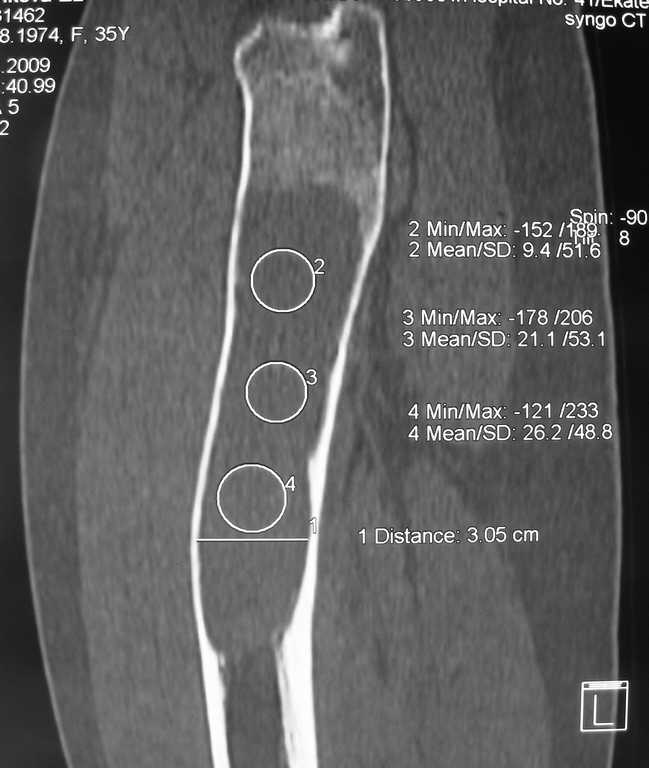

Уважаемые коллеги, доброго времени суток!

Большое спасибо всем, откликнувшимся на сообщение от 17 ноября

"Фиброзная дисплазия". В настоящее время пациентке выполнена

компьютерная томография и открытая биопсия правой бедренной кости с

последующим иммуно-гистохимическим исследованием.

Подтверждается диагноз фиброзной дисплазии без малигнизации.

Хотелось бы услышать мнение коллег относительно тактики дальнейшего

лечения пациентки, в первую очередь, варианты замещения дефекта в

случае резекции патологического очага с учётом обширности поражения.